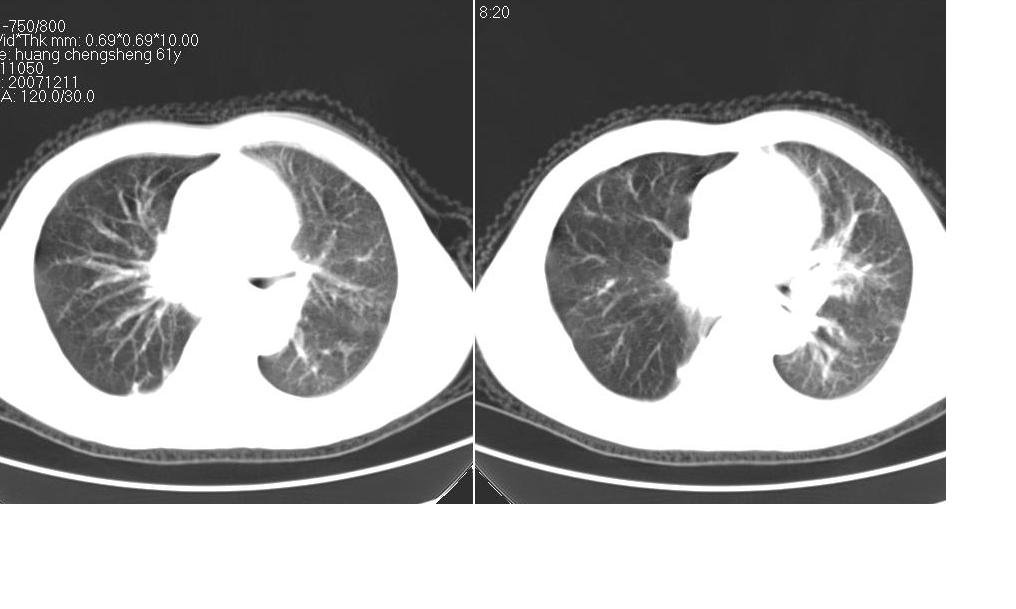

男 61岁,已确诊肺癌半年余.

右肺小细胞肺癌并纵隔淋巴结转移。胸腔积液,心包少量积液。左肺改变不除外癌性淋巴管炎

考虑:1、右肺下叶中心型肺癌并纵隔淋巴结转移。胸腔积液。

2、心包少量积液。

3、左肺改变不除外癌性淋巴管炎或化疗后肺间质纤维化。

纵隔及右肺门淋巴结肿转移,右肺改变是否为阻塞性肺气肿改变?左肺改变支持淋巴管炎的诊断;化疗后肺改变应该双肺都有改变。

支持!另:右肺癌性淋巴管炎!

1 右肺下叶中心型肺癌.纵隔内淋巴结转移.右侧胸腔积液. 2 心包少量积液.3 肺间性改变考虑与化疗有关.